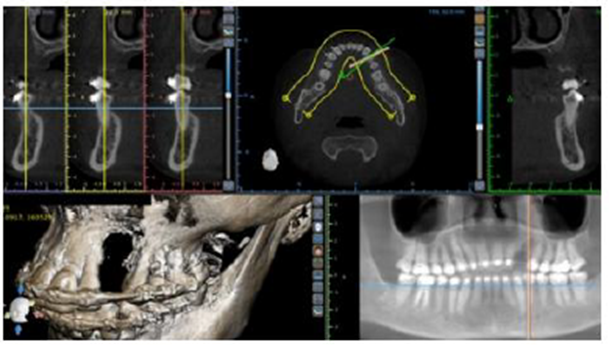

Paciente do sexo feminino, 30 anos, foi encaminhada para restauração com implante na região do canino superior esquerdo. Para obter uma avaliação precisa do volume ósseo tridimensional, foi realizada uma tomografia computadorizada Cone Beam que revelou uma deficiência óssea vertical (Figura 1).